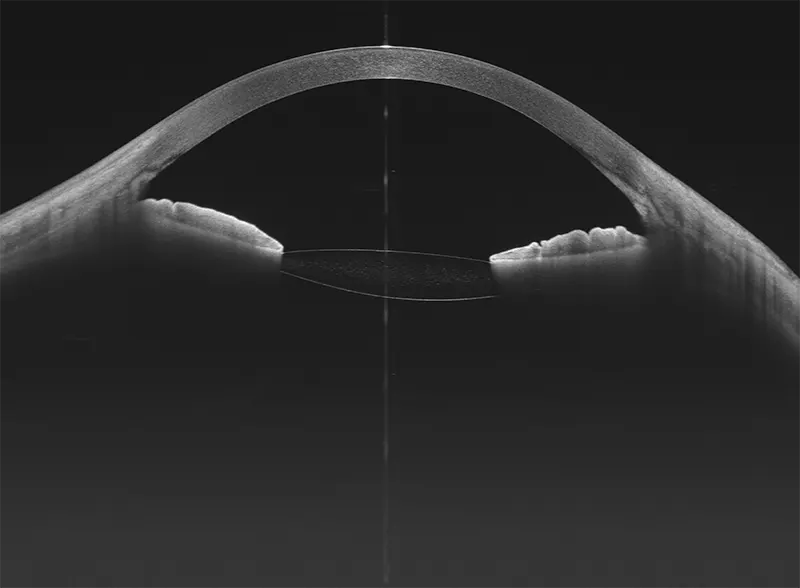

Galería OCTs del TowardPi Yalkaid